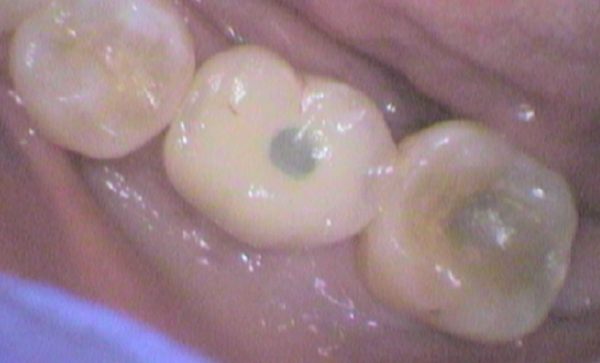

Case 25